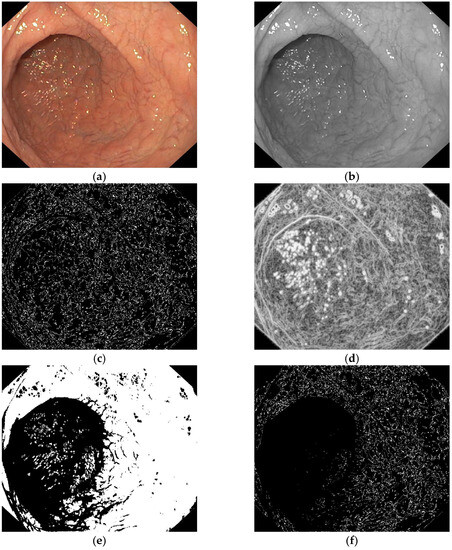

- Entropy filter applied on the gray level image;

- Binarization of the entropy-filtered image with high and low thresholds;

- Binarization of the gray level image using two high and low thresholds;

- Logic AND between binary images and dilatation;

- Patches selection according to the final binary image and the gray level range.